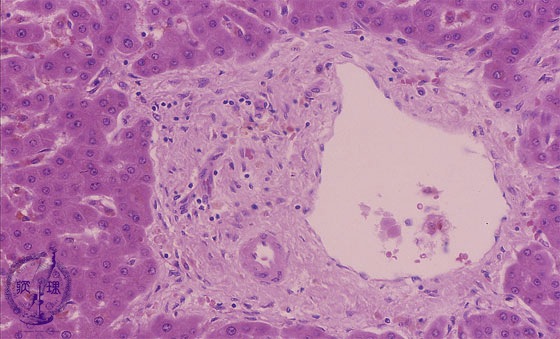

• 10.Liver

• (11)Transplantation rejection

Microscopic image (HE stain, high power view): Slightly expanded, mid-sized portal areas contain branches of portal vein and hepatic artery, but interlobular bile ductules are absent. Inflammatory cell infiltration is minimal.